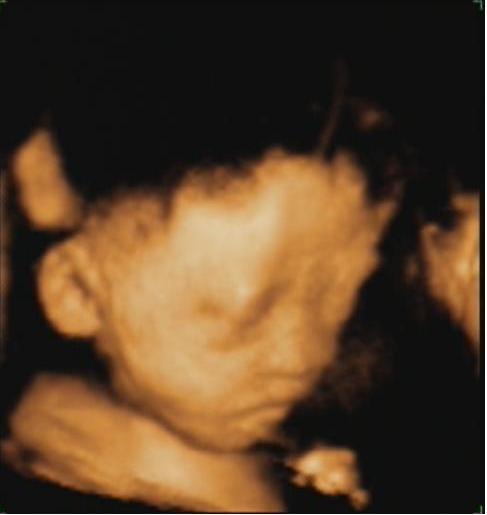

奇妙的胎, (Lo阿伶)